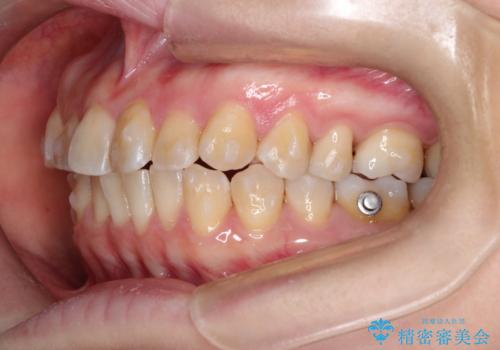

【インビザライン 】前歯の凸凹をなおしたい

- 前歯の凸凹を主訴に来院されました。

インビザライン にて治療を行い、歯並びが綺麗になったと満足していただきました。

前歯のガタガタの量が多かったため、IPR(歯のサイズを小さくするための処置)を行なって治療しました。